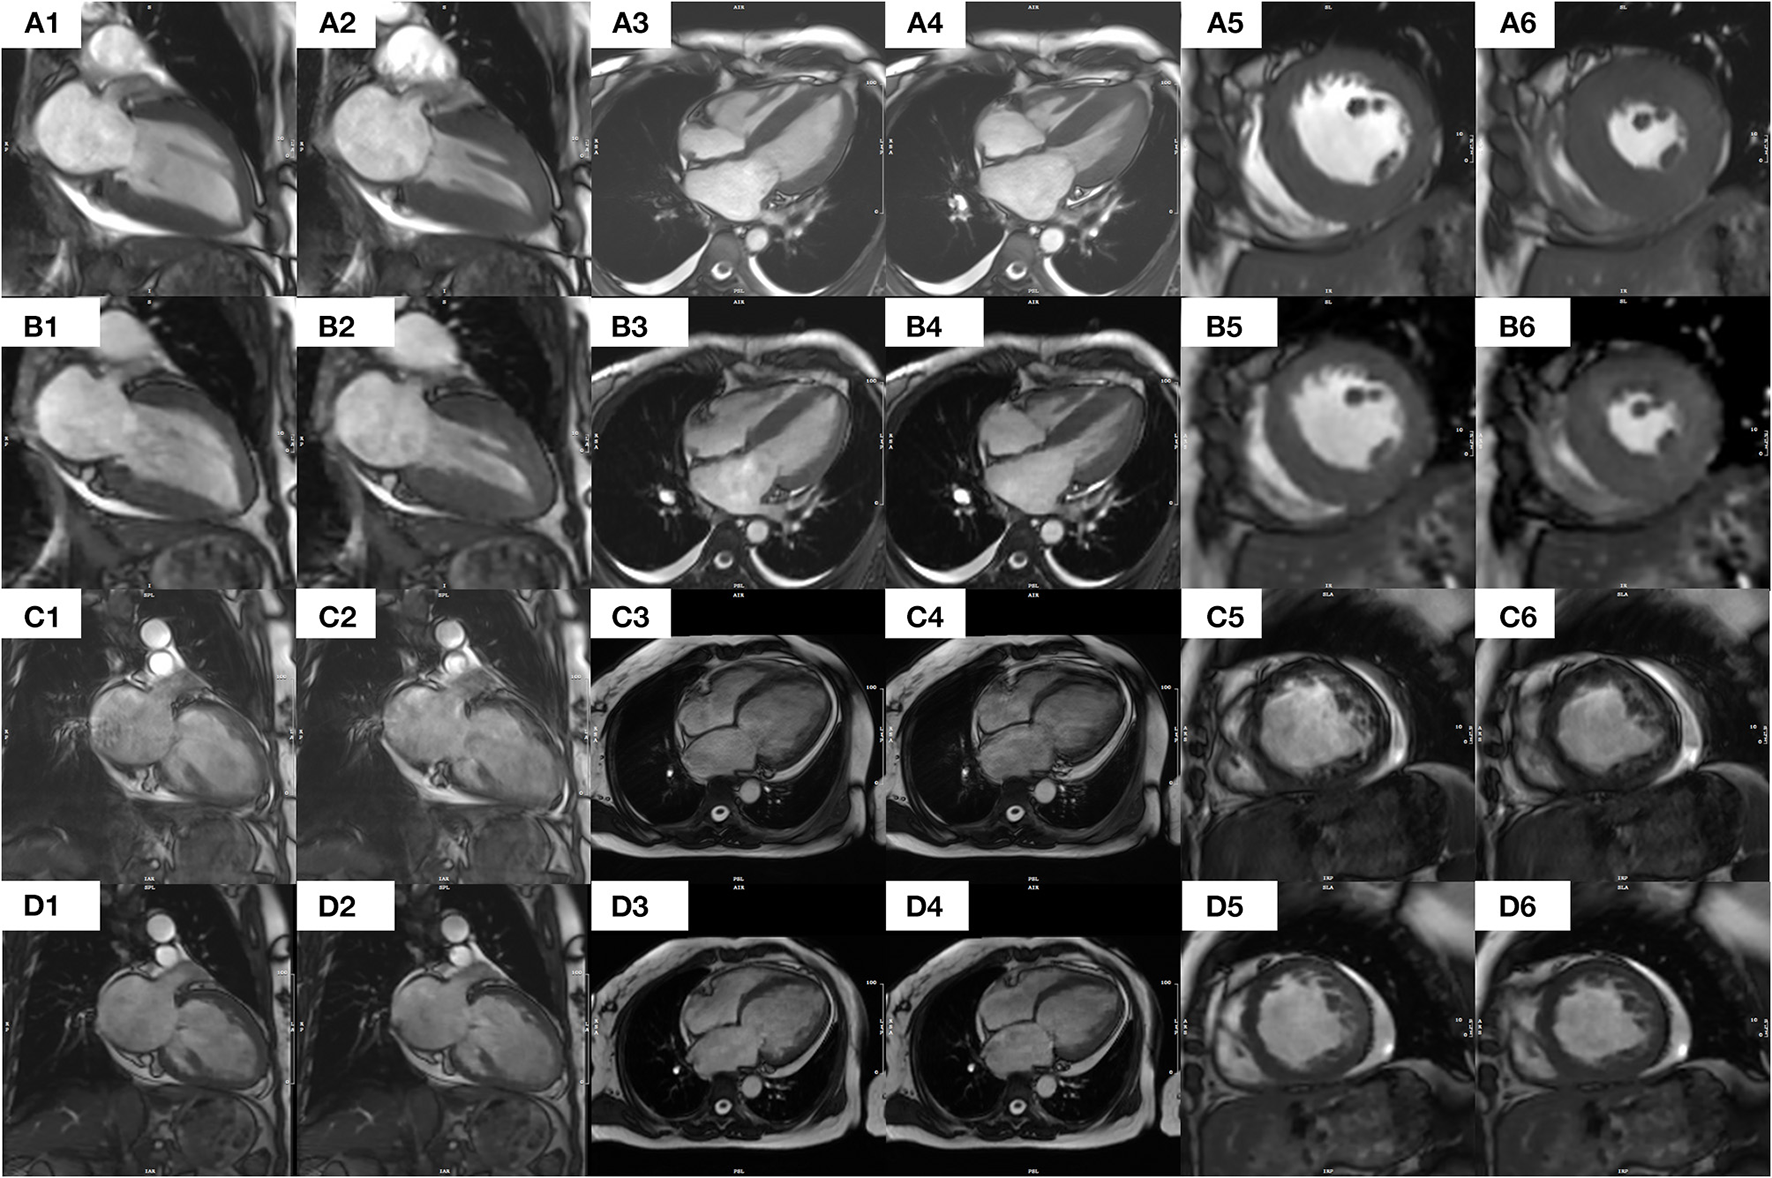

In all 36 patients with NSR, the segmented cine image quality score was higher than that of the CSRT cine (3.79 ± 0.36 vs. 3.12 ± 0.39, respectively; p < 0.001). In contrast, in all 35 AF patients, the CSRT cine image quality was higher than that of the segmented cine (2.96 ± 0.61 vs. 1.90 ± 0.70, respectively; p < 0.001). In all 71 patients (including both NSR and AF), there was no significant difference in image quality between CSRT and segmented cine (3.04 ± 0.52 vs. 2.86 ± 1.10, respectively; p = 0.152). All images of both sequences in NSR and CSRT sequence in AF were regarded as diagnostic images, but almost half of the AF patients (17 of 35) had a segmented cine image quality score lower than 2 (nondiagnostic). Interobserver agreements for the image quality regarding segmented cine and CSRT cine from all patient data were 0.870 and 0.872 (in NSR), 0.943 and 0.934(in AF), respectively. Representative images from the two sequences in patients with NSR and AF are provided in Figure 3.

Figure 3

Images of segmented and CS real-time bSSFP cine sequences from a patient with NSR [(A1–A6) and (B1–B6), respectively] and a patient with AF [(C1–C6) and (D1–D6)]. Specifically, in a 41-year-old female patient with NSR, each image from a segmented cine in end diastolic (A1) or end systolic (A2) 2CH, end diastolic (A3), or end systolic (A4) 4CH, or end Diastolic (A5) or end systolic (A6) middle SA appears clearer and sharper than the corresponding images from a CS real-time cine [(B1–B6), respectively] In contrast, in a 54-year-old female patient with AF, the images of a segmented cine appear blurrier and of lower diagnostic value. Specifically, each image from a CS real-time cine in end diastolic (D1) or end systolic (D2) 2CH, end diastolic (D3) or end systolic (D4) 4CH, or end diastolic (D5) or end systolic (D6) middle SA appears clearer and sharper than the corresponding images from a segmented cine [(C1–C6), respectively]. An additional movie file shows this in more detail. CS, compressed sensing; bSSFP, balanced Steady-State-Free-Precession; AF, atrial fibrillation; NSR, normal sinus rhythm; 2CH, two-chamber; 4CH, four-chamber; SA, short axis.